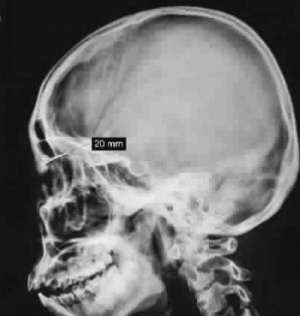

两个月前,小陈在当地医院矫正牙齿拍摄头部X片时,惊讶地发现左眼眶内有异物存在。焦急万分的父母带着女儿四处求诊,均因异物滞留眼眶内时间太久而不敢贸然手术。辗转多家医院后,父母带着女儿慕名来到长征医院眼科求治。

经检查会诊,医生在小陈眼睛上缘发现一根长条钩针,针头“斜插”进入额骨,唯一的办法是开刀取出钩针,但由于经过16年的积淀,钩针已经生锈腐蚀,与周围组织粘连;同时因为针头有倒钩,钩子下方还有一个活动的“小门”。贸然拔出可能会把周围神经和血管以及硬脑膜钩伤,造成大出血、眼睛失明以及脑脊液漏,且随时有折断的可能,手术风险很大。

为了能安全取出异物,考虑到金属异物在眼眶内的定位比较复杂,且存留时间较长后易与周围脑组织形成粘连,为避免对眼眶及脑组织产生较大创伤,术前,经过三维立体定位、X扫描并生成相应的坐标,对异物实施“精确打击”。术中,魏锐利主任在显微镜下锁定目标后,用显微手术缓缓地在接近筛窦处的肉芽组织中进行剥离,同时保护好周围血管和神经,终于露出了黑褐色的金属异物。经过2个小时手术,一根尖端嵌入颅内的钩针终于被成功取出来了,小陈左眼视力没有受到任何影响。  (施捷)

X片显示针头“斜插”进入额骨(资料照片)